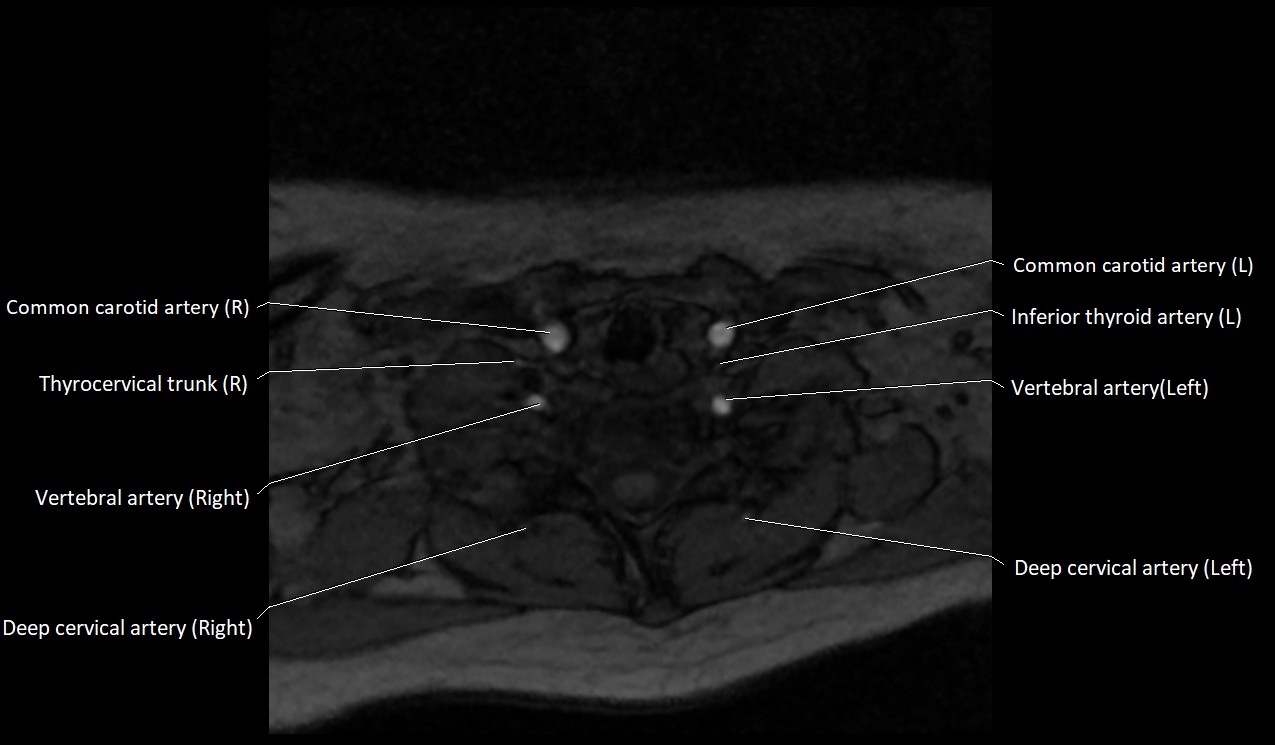

MRI images

image